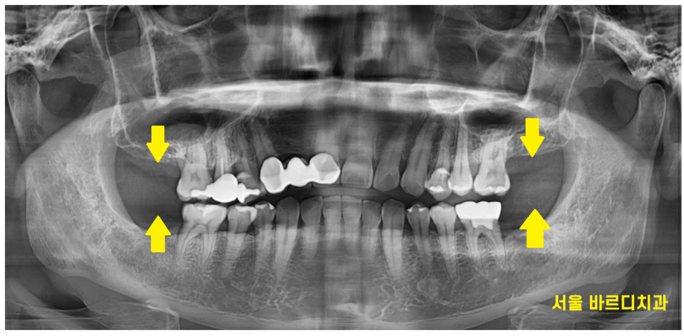

ct를 분석해 보니

치아가 똑같이 양쪽으로 없었어도

오른쪽 왼쪽 남아있는 뼈의 양이 다르네요~~

오른쪽이 왼쪽에 비해서

뼈가 더 없었는데

본능적으로 환자분께서 느껴지셨던 것 같습니다.